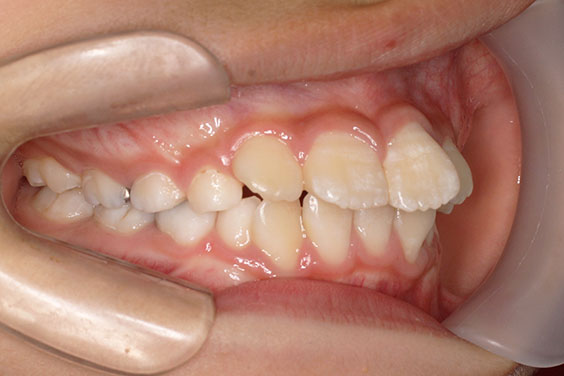

歯が重なっている、出っ歯を治したい 以前に治療した方からの紹介で来院した患者さんです。 上下顎前歯部の叢生(がたつき)、上下顎前歯の前方傾斜、 骨格的上顎前突傾向でした。 小児矯正で叢生の緩和を行い、 本格矯正で前方傾斜した前歯の改善を行いました。 マルチブラケット 動的治療期間 3年3か月 調整回数25回